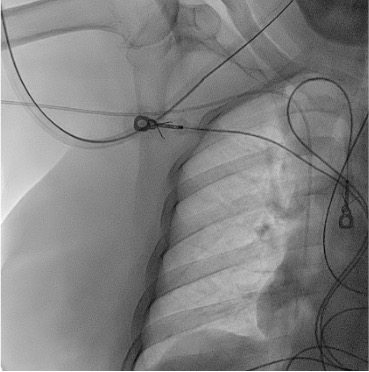

View final PICC position

Fluoroscopy showing PICC tip at cavoatrial junction

• Target tip position: Lower 1/3 SVC / cavoatrial junction

• Right-sided PICC: Tip at level of tracheal bifurcation (carina) on CXR

• Left-sided PICC: Must be advanced 1–2 cm deeper than right-sided (longer path through innominate vein before descending to SVC)

• Confirm catheter tip on fluoroscopy prior to use. Right-sided: cavoatrial junction. Left-sided: lower SVC / cavoatrial junction (1–2 cm deeper than right).